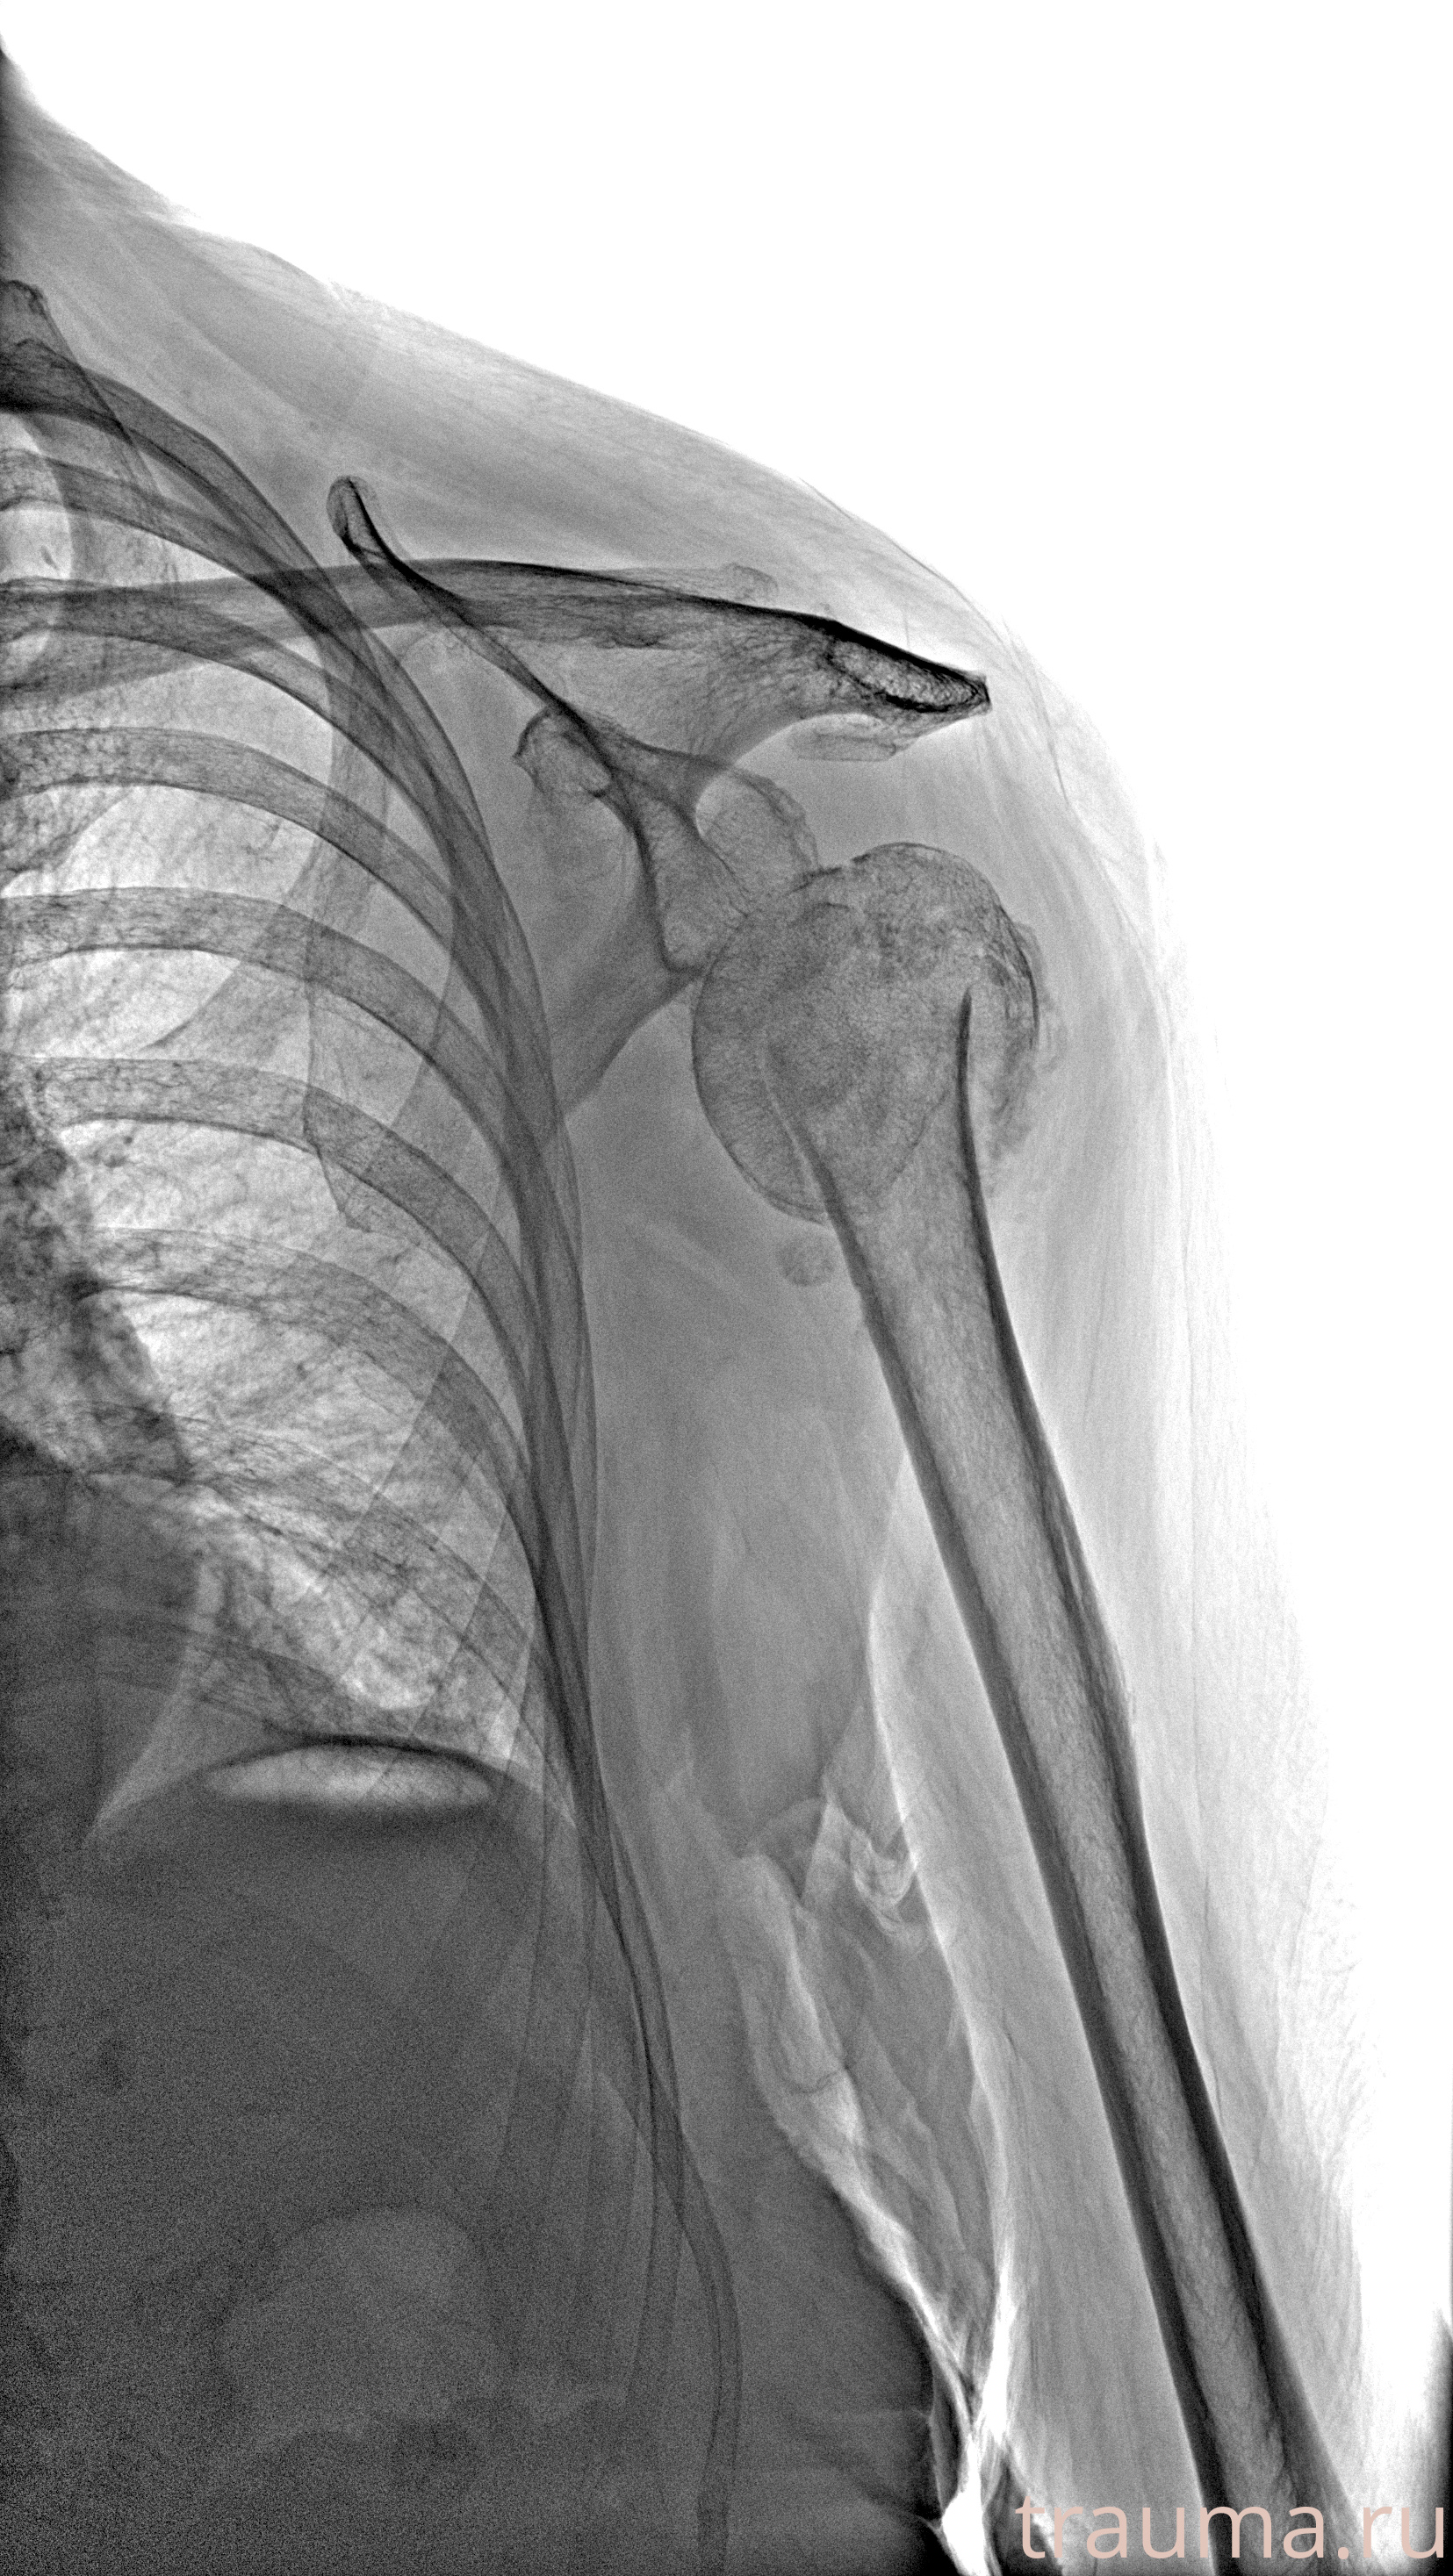

Рентген на дому: по вашему адресу приезжает врач-рентгенолог, травматолог-ортопед с мобильным рентгеновским аппаратом, проводит диагностику травмы или заболевания, делает необходимые рентгенограммы, дает рекомендации по дальнейшему лечению. Получить качественные снимки в домашних условиях возможно благодаря уникальной методике, разработанной МосРентген Центром для института  Склифосовского